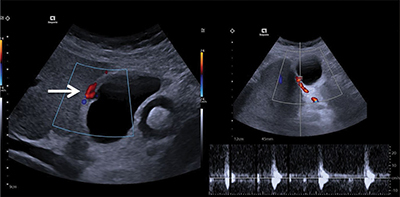

Teaching point: Cystic artery pseudoaneurysm is a rare condition that should be considered in patients with unexplained abdominal pain, a history of gallbladder disorders, or signs of hemorrhage, and can be diagnosed by Doppler ultrasound.